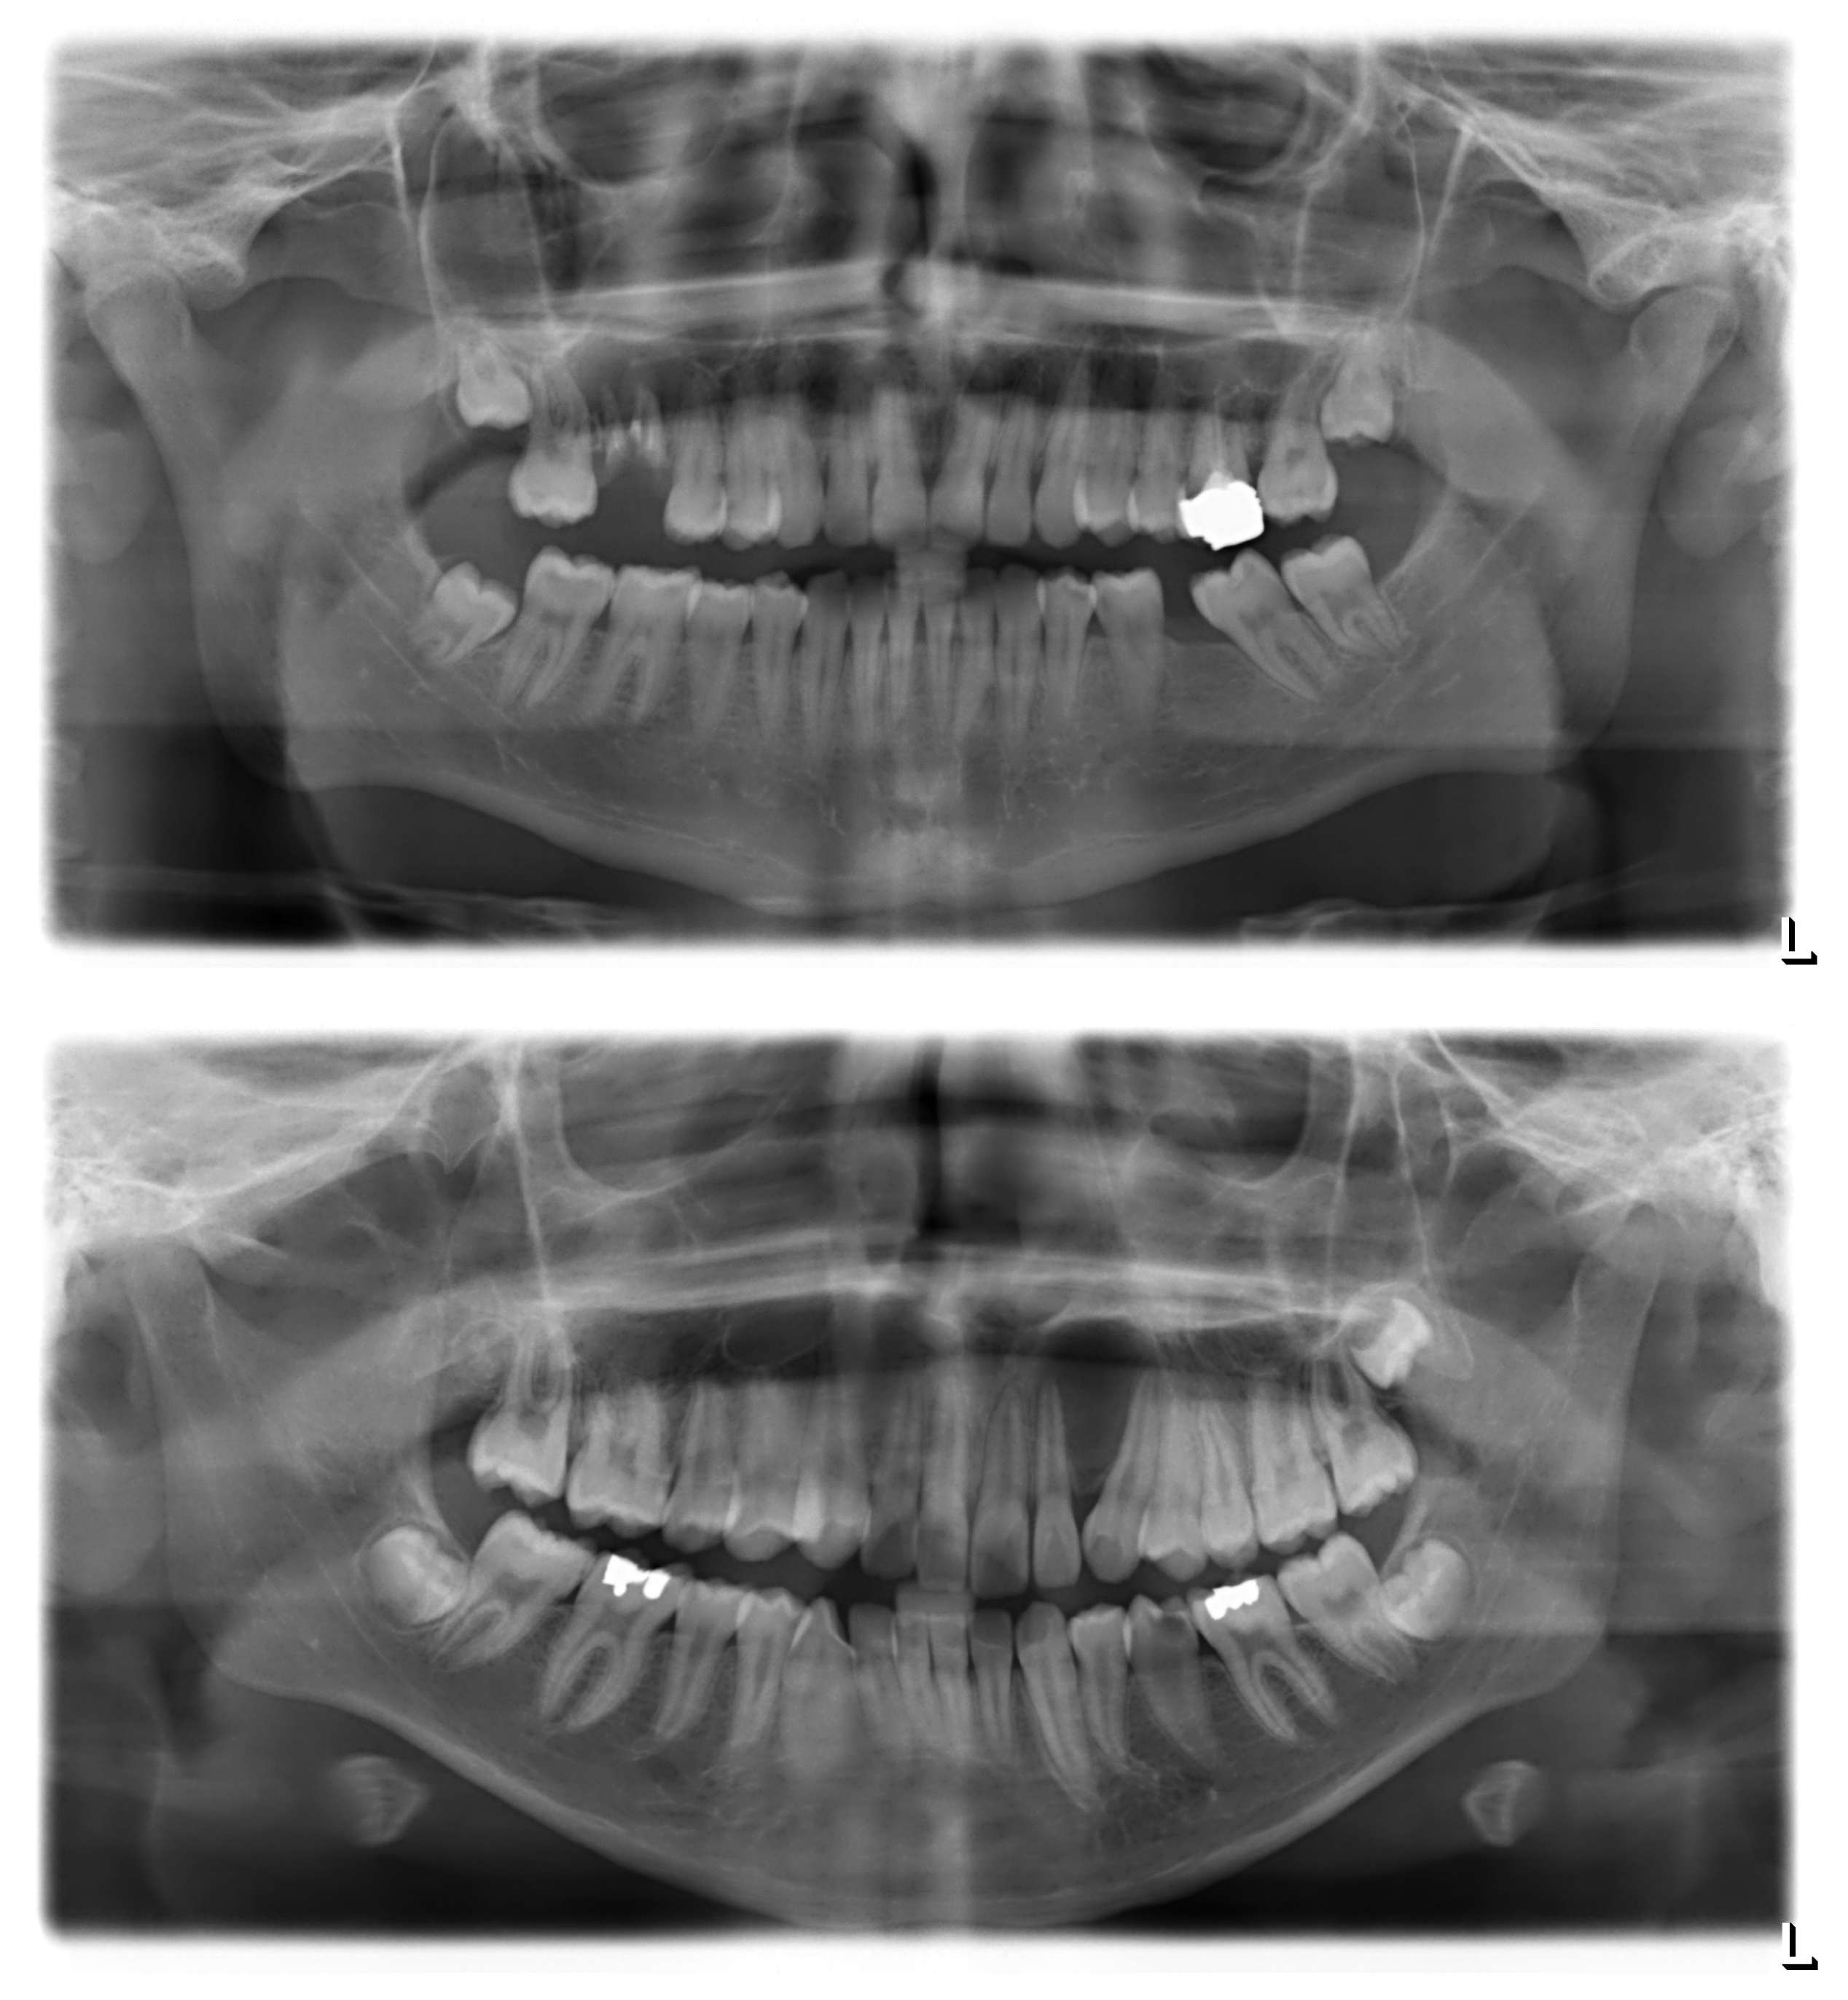

Figure A1.

Sample panoramic radiographs for odontogenic and non-odontogenic cysts. Top, odontogenic (radicular) cyst at the upper right first molar. The radiolucency appears centered around the roots of the affected tooth, which clearly shows multiple signs of pathology. Bottom, non-odontogenic (globulomaxillary) cyst between the upper left lateral incisor and canine. There is no sign of primary pathology of either the incisor or the canine; their displacement is an assumed consequence of cystic growth.